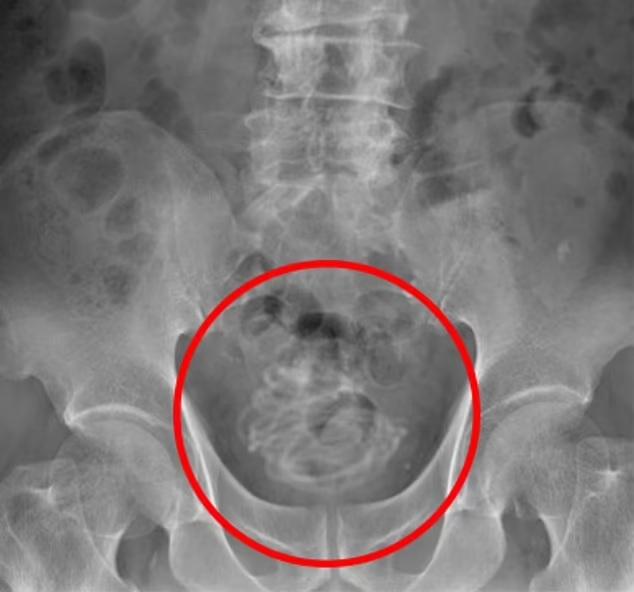

精神病學期刊《Psychiatry Research Case Reports》刊登了一個案,指斯里蘭卡一名17歲少年,因下腹疼痛和排尿困難求醫。X光一照發現他陰莖有異物,醫生最後從其陰莖取出一條8吋長電線。個案刊登在精神病學期刊,因少年向醫生坦承為了性快感,塞異物入陰莖,並沉迷其中,每天這樣自慰3次。醫生將他轉介到精神科醫生治療這種塞異物的「性癮」。

報道指那名少年忍痛9天才去求醫,醫生為他取出電線後,他沒有其他健康問題。他入院後數天才告訴醫生,在過去兩年來一直有這種自慰習慣,通常都能夠取出異物。他出現自慰上癮的跡象,承認每天這樣做3次,想「斷癮」但卻難以自控。塞異物入生殖器官非常危險,有機會引起嚴重感染,導致膀胱組織壞死。據悉,那名少年有社交恐懼並害怕拍拖,心理醫生向那名少年開了一種抗抑鬱藥,治療他的性欲錯亂症,但自他出院後與其失去聯絡,他也未有再尋求心理治療,未知他能否控制性癮。